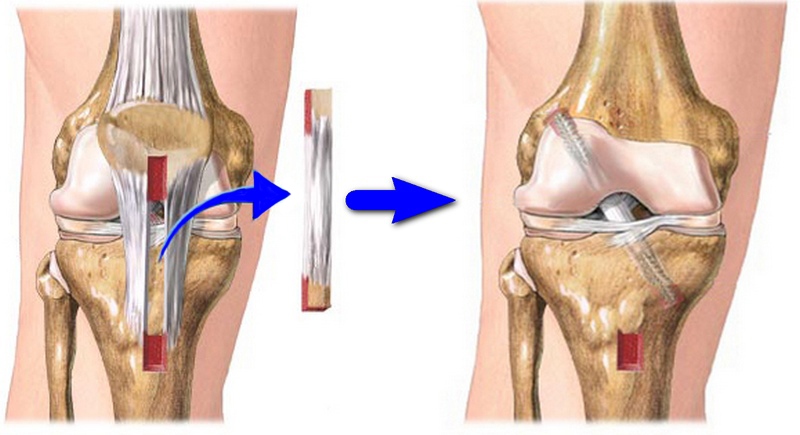

Если нарушается целостность соединительных тканей, проводят малоинвазивную процедуру — артроскопию. При полном разрыве связок может потребоваться реконструкция. В этом случае выполняется сшивание волокон, если травма произошла не более трех недель назад, или фиксация пучка с помощью сухожилия соседней мышцы. После операции необходимо длительное восстановление:

- физиотерапия;

- массаж;

- лечебная физкультура.

Продолжительность реабилитации составляет от 14 до 16 недель. Умеренные физические нагрузки допустимы уже через 10 дней после операции. Важно своевременно начать разработку сустава, чтобы избежать атрофии и некроза мышц. Не рекомендуется самостоятельно проводить процедуры и выполнять упражнения в период восстановления.